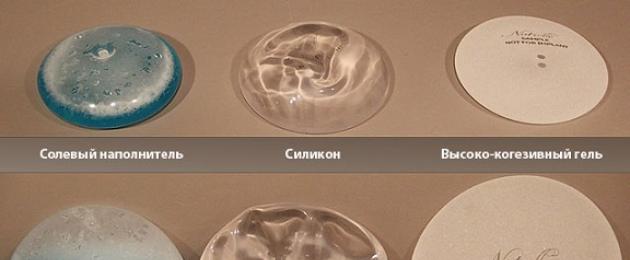

Анатомические импланты Eurosilicone

Раздел: Визуальный дайджест